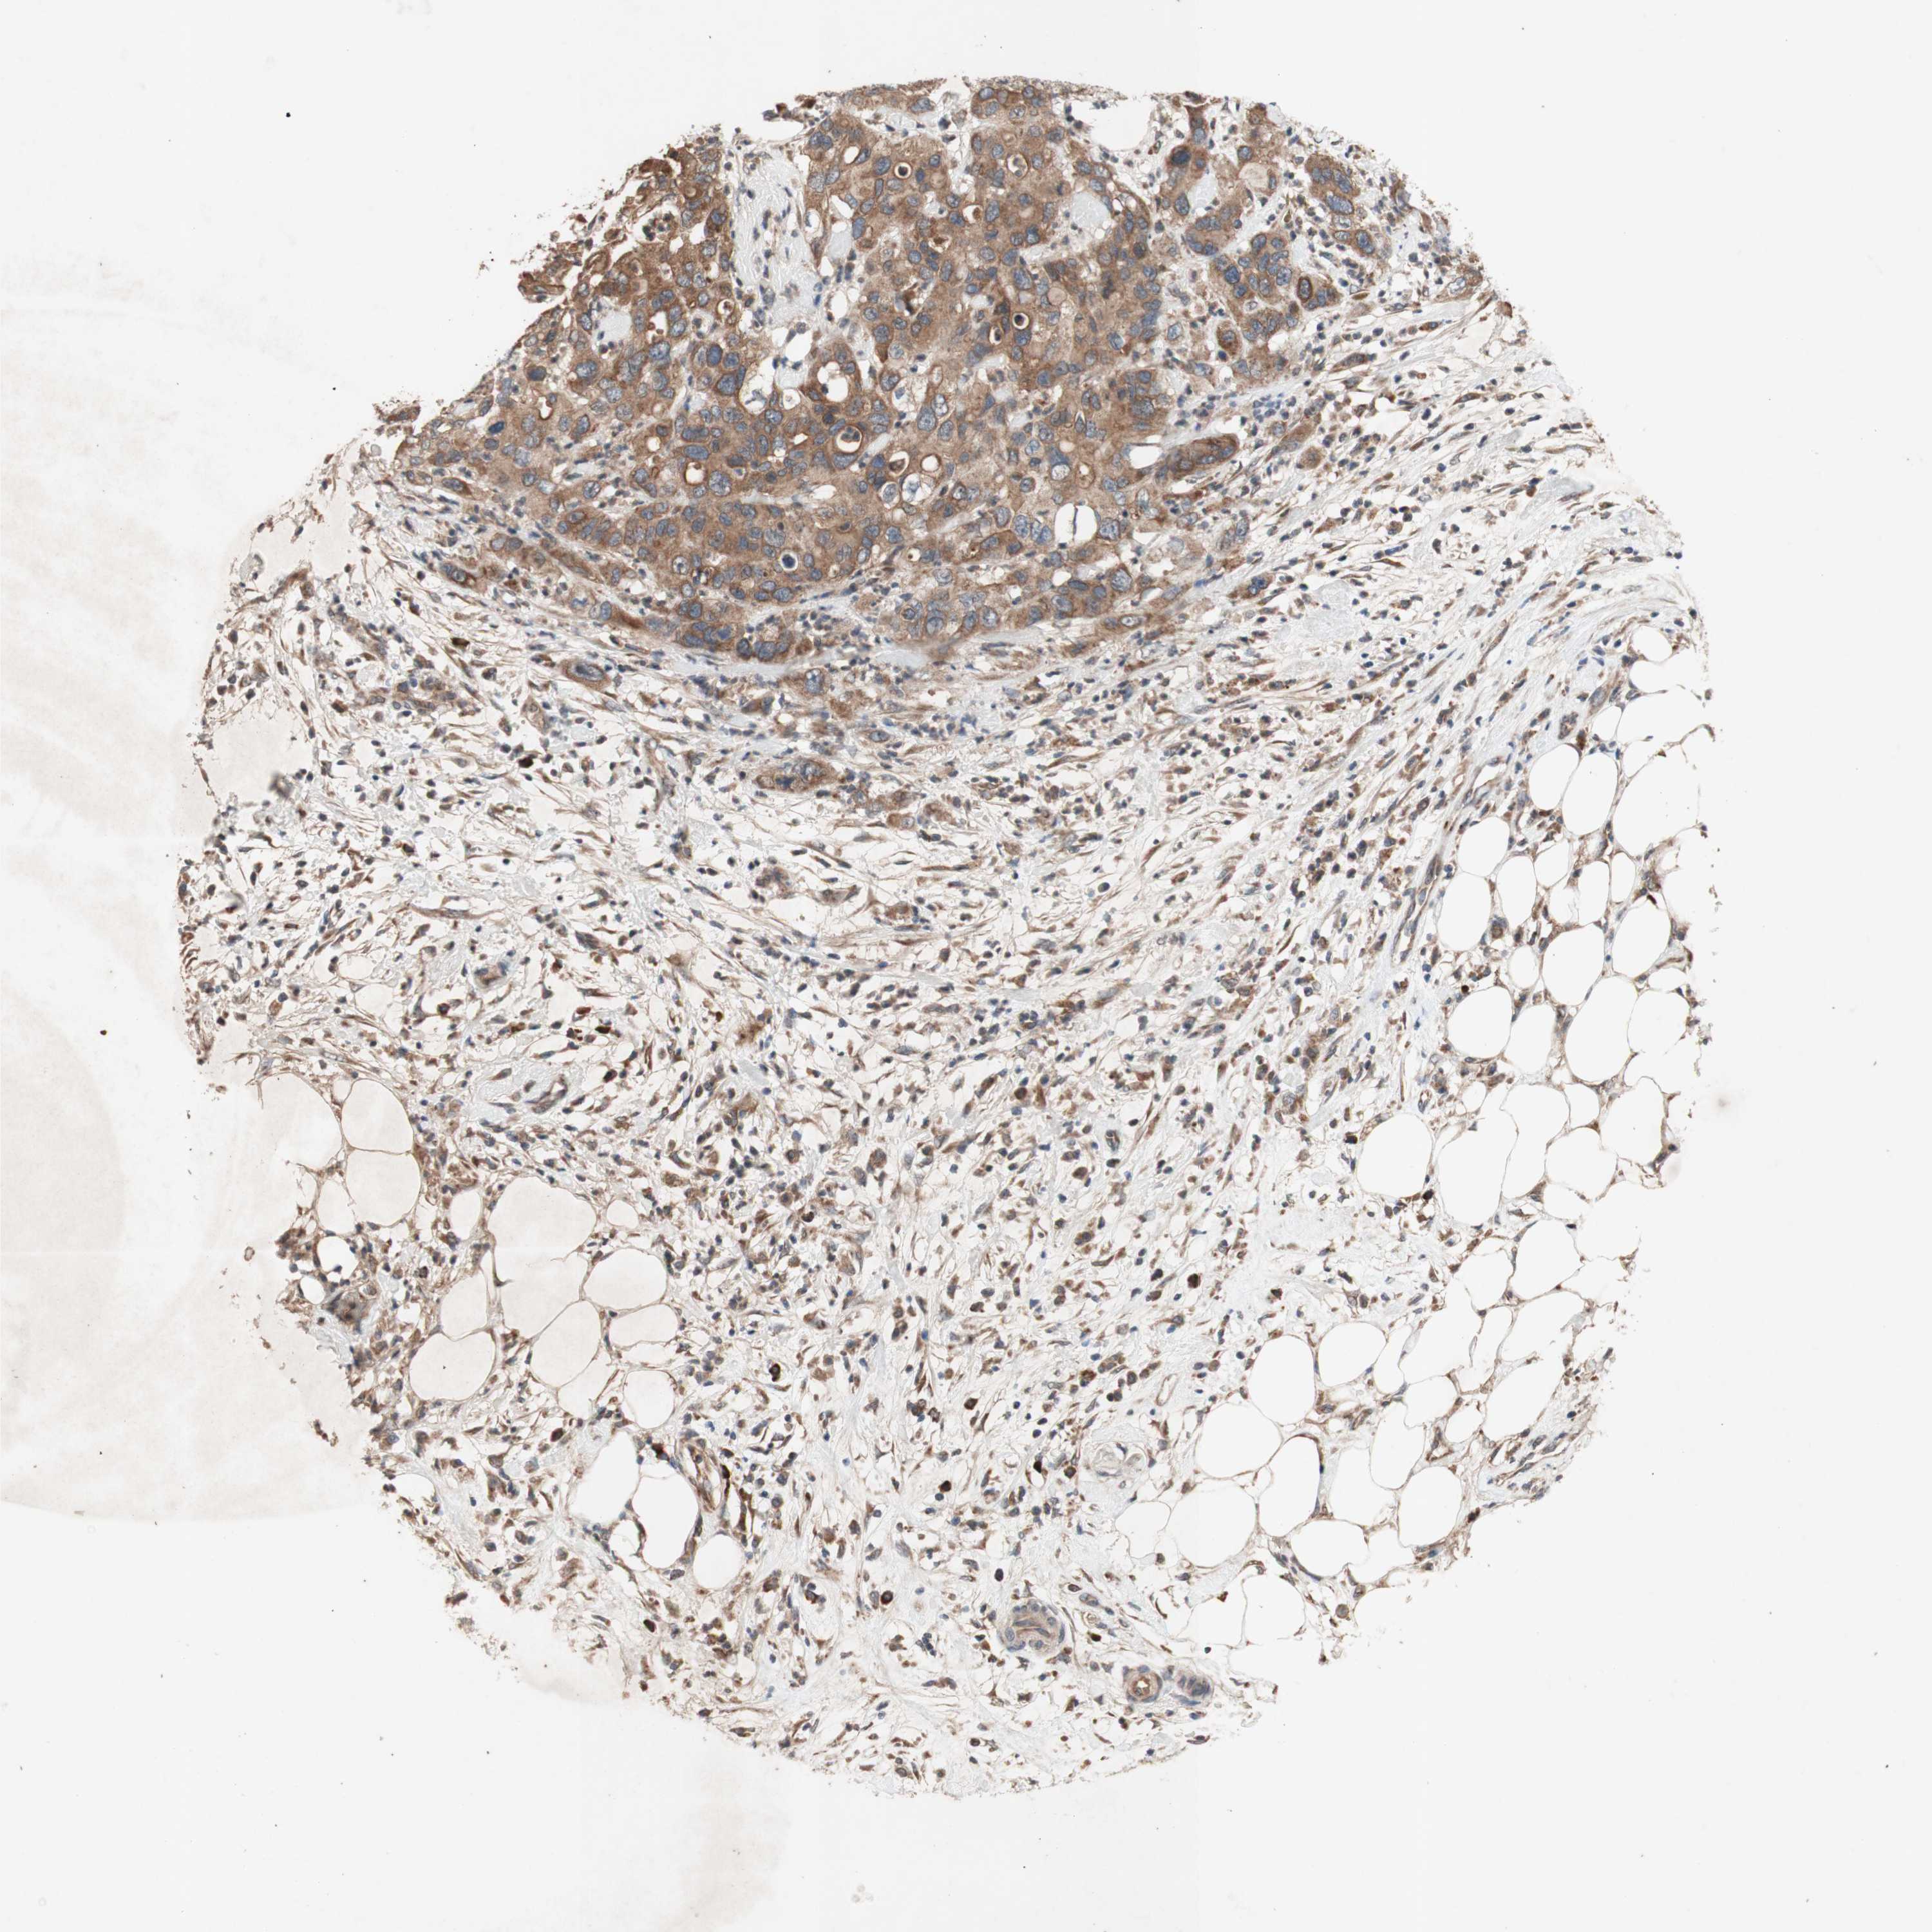

PANCREATIC CANCER - Protein expressioni

A mouse-over function shows sample information and annotation data. Click on an image to view it in a full screen mode. Samples can be filtered based on level of antibody staining by selecting one or several of the following categories: high, medium, low and not detected. The assay and annotation is described here.

Note that samples used for immunohistochemistry by the Human Protein Atlas do not correspond to samples in the TCGA dataset.

Antibody stainingi

Antibody staining in the annotated cell types in the current human tissue is reported as not detected, low, medium, or high, based on conventional immunohistochemistry profiling in selected tissues. This score is based on the combination of the staining intensity and fraction of stained cells.

Each image is clickable and will lead to virtual microscopy that enables deeper exploration of all samples and also displays staining intensity scores, fraction scores and subcellular localization as well as patient and tissue information for each sample.

Antibody HPA046841

Antibody HPA052867

Antibody CAB009746

Staining

High

Medium

Low

Not detected

Intensity

Strong

Moderate

Weak

Negative

Quantity

>75%

75%-25%

<25%

None

Location

Nuclear

Cytoplasmic/membranous

Cytoplasmic/membranous,nuclear

Adenocarcinoma, NOS

Adenocarcinoma, metastatic, NOS